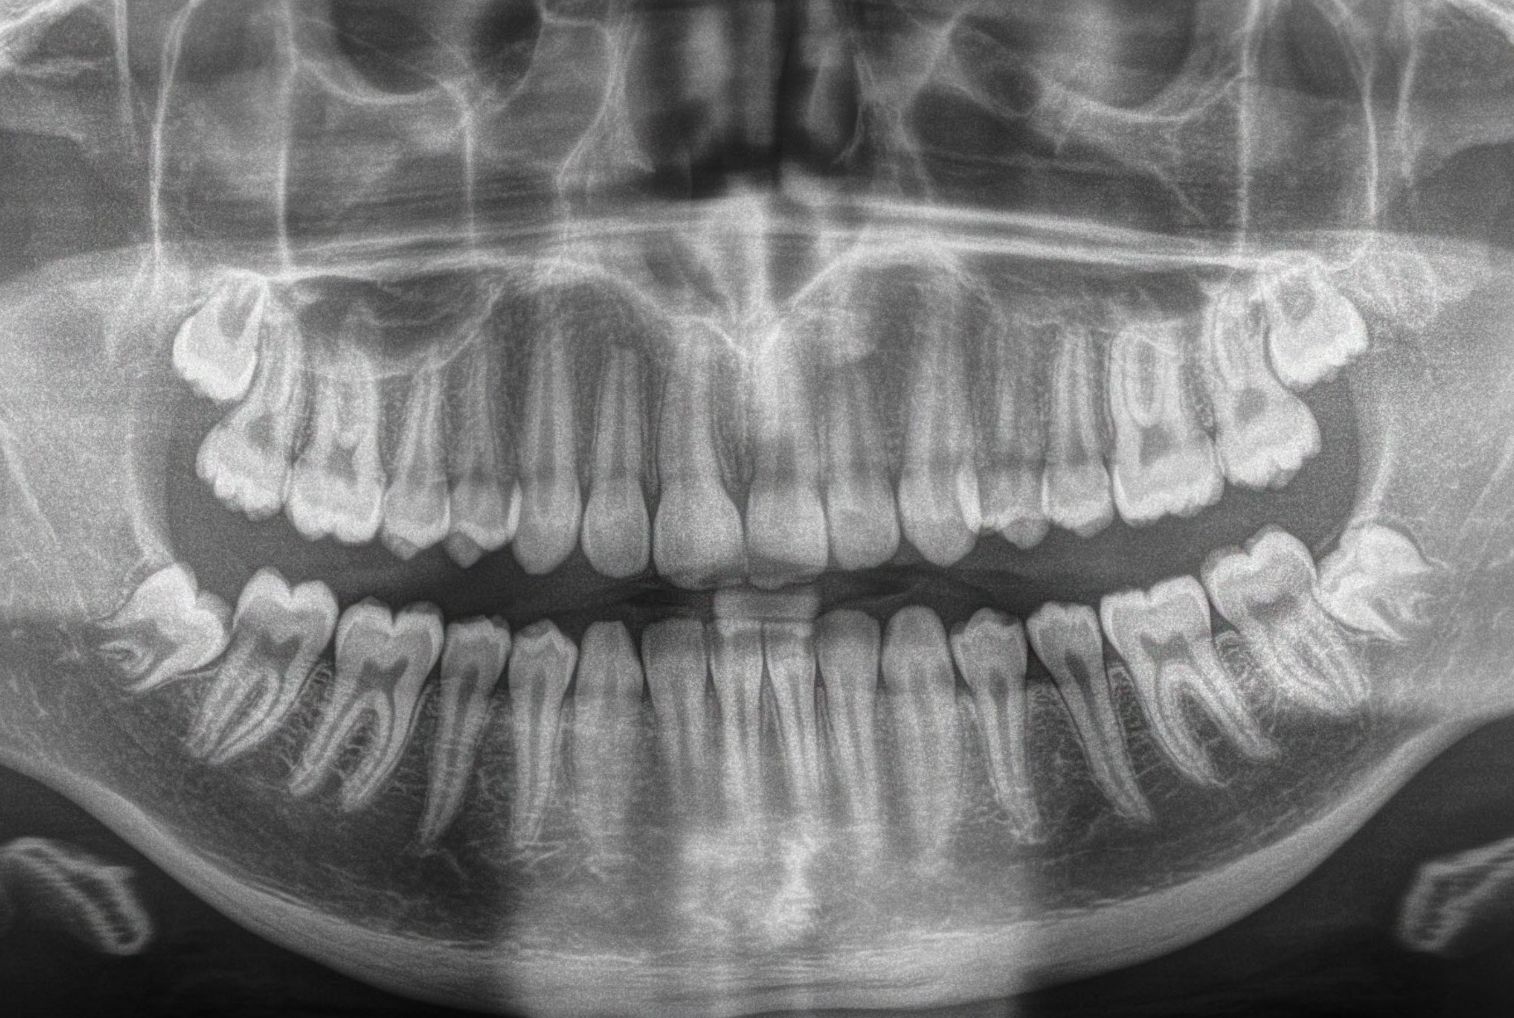

Explore 75+ detailed third-molar case studies, organized by difficulty to sharpen your diagnostic skills and guide case selection. Learn key red flags and follow step-by-step walkthroughs for efficient, predictable extractions.

The O.S. Accelerator course gradually builds your confidence and skills in a step-by-step progression assuming no prior knowledge of third molar extractions.  Upon completion of the third molar content, you'll instantly be able to recognize cases that can be managed vs. those that should be referred.  You will also instantly recognize the approach to take and instruments to use for the common types of impactions including mesioangular, distoangular, horizontal, and vertical.